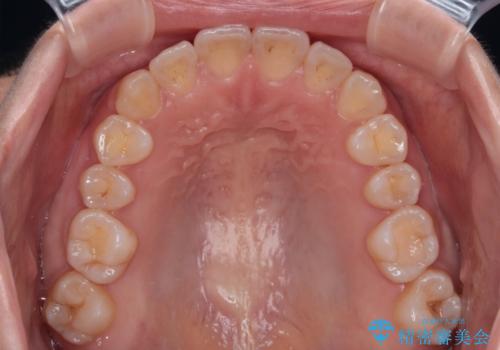

舌の突出癖により上下前歯が開咬となりましたが、舌のトレーニングと顎間ゴムの使用により、元々の被蓋関係に改善することができました。

アンカースクリューを用いて、出っ歯仕上がりを回避し、正中位置も改善することができました。